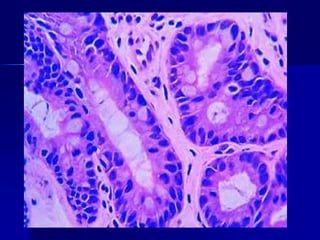

Adenocarcinoma gástrico.

A. Adenocarcinoma de tipo

intestinal compuesto por células

cilíndricas y formadoras de glándulas

que infiltran a través del estroma

desmoplásico.

B.En los tumores infiltrantes,

las células en anillo de sello (difuso)

pueden ser reconocidas por sus grandes

vacuolas de mucina citoplásmica y sus

núcleos delgados falciformes,

desplazados hacia la periferia.

Obsérvese la ausencia de formación de

glándulas